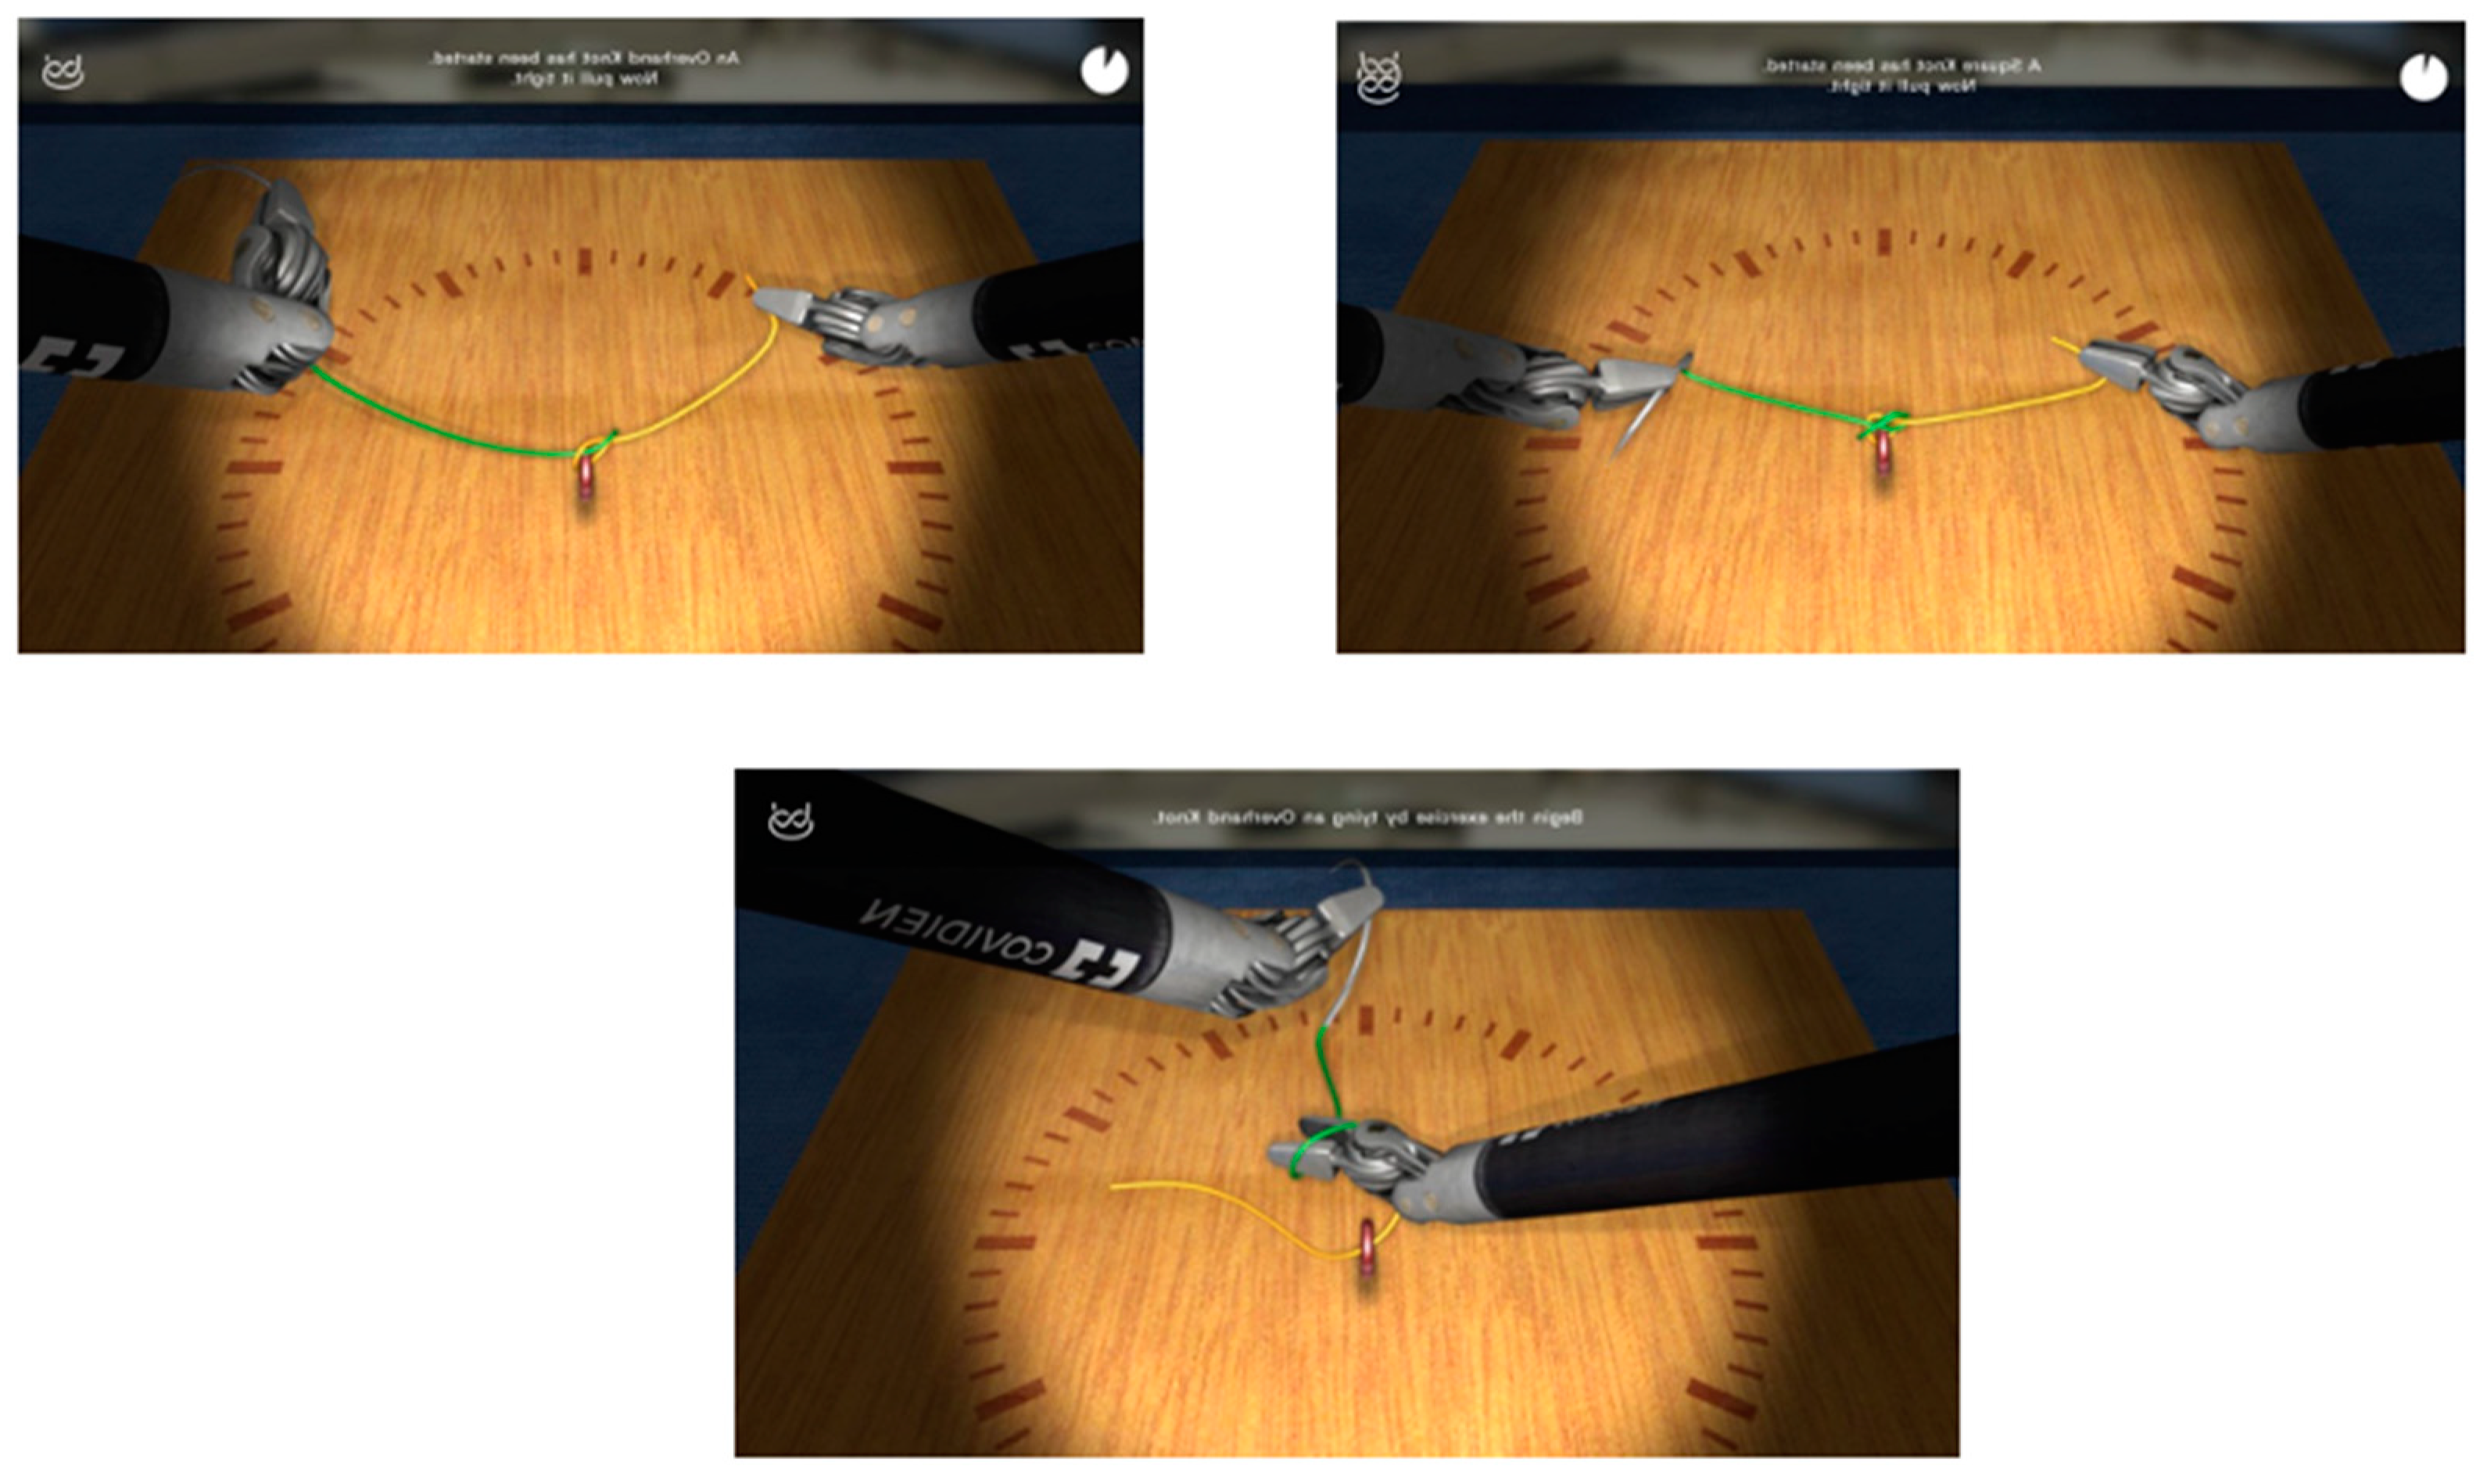

2.2. Training Session